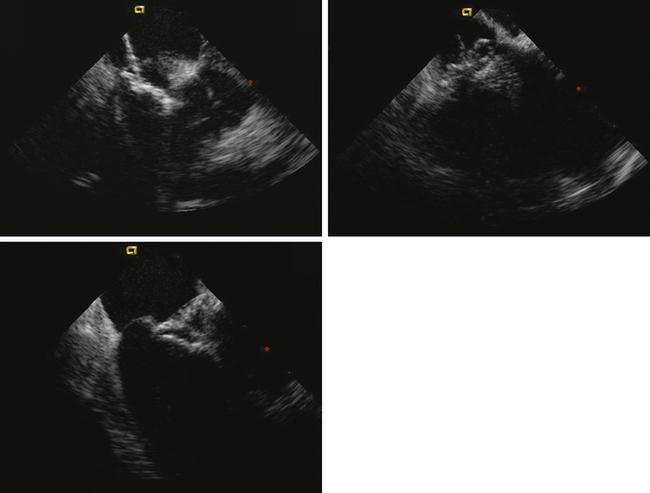

ICE can be helpful in patients with a prosthetic mitral or aortic valve, or both, in whom the left ventricular outflow tract or inferior aspect of the mechanical aortic valve needs to be imaged. Shadowing from the prosthetic valves, a common problem with either surface or transesophageal imaging, can be minimized with ICE imaging. Fig. 21-18 shows a series of ICE images in a patient with a prosthetic aortic valve and mitral annuloplasty who developed subaortic stenosis confirmed with ICE.